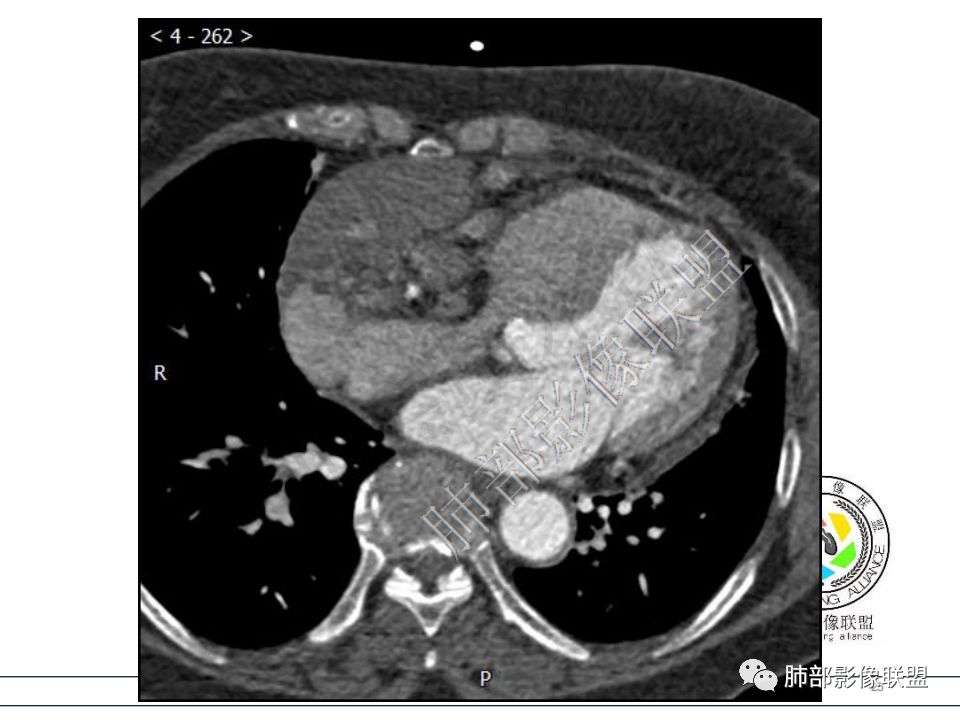

病例一考虑心包来源,病灶从大动脉根部一直延续到心底,明显不均匀强化,没有心包积液,良性?边缘强化,良性先考虑血管瘤。

病变位于心包,密度较低,边缘结节性强化,猜一个血管瘤。 医学百科网 | YxBaike.Com

定位心包,局部与右心房分界不清,右心房受压,冠脉受压,渐进性强化,没有心包积液,考虑心包来源或右心房游离壁来源血管瘤。 医学百科网 | YxBaike.Com

从心底沿右侧房室沟一直延伸至近膈面,心包来源可以解释的通;另外病变与右心室右心房之间的脂肪间隙一直存在。

右冠进入病灶内。 医学百科网 | YxBaike.Com

右冠增粗参与供血吧?

心包海绵状血管瘤的CT特征为平扫呈边界清楚的圆形或者类圆形低密度肿块,对比增强扫描是诊断海绵状血管瘤的关键。动脉期肿瘤边缘可出现散在斑片状、结节状明显强化灶,接近同层强化大血管密度。静脉期散在的强化灶相互融合同时向肿瘤中央扩展。 医学百科网 | YxBaike.Com

渐进性强化,边界清晰,周围脂肪间隙存在,没有心包积液。 医学百科网 | YxBaike.Com

边界清晰,周围脂肪间隙存在,临近器官受压无受累。 医学百科网 | YxBaike.Com

对的,心包太硬,很难突破。这例压迫右房、三尖瓣环。 医学百科网 | YxBaike.Com

冠状静脉窦增粗,下腔粗,回心血流受限,影响右心舒张,相当于右心衰。 医学百科网 | YxBaike.Com